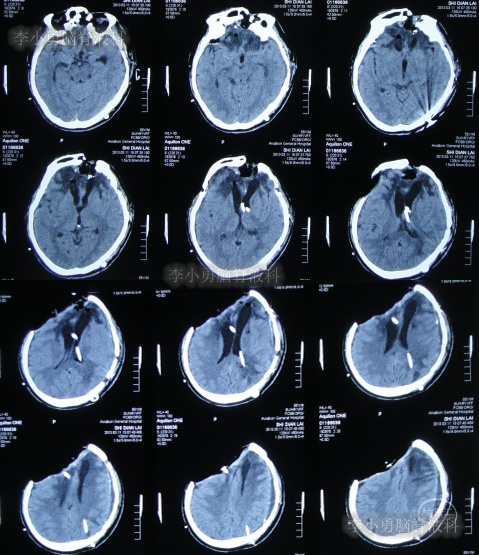

2012年11月1日(开颅术后126天即脑室腹腔分流术16天),转住入李小勇脑脊液科入院时:神志模糊,表情淡漠,肢体不能遵嘱活动,时常有癫痫发作;右额颞顶颅骨缺损,缺损相应区域局部凹陷,自右侧鼻唇沟至头顶有一疤痕,右侧额面部颅骨凹陷(图-6)。头颅CT:脑室腹腔分流术后改变,脑室扩张(图-7)。

图-7:入院时头颅CT

2012年11月5日(入院后5天),进行了原脑室腹腔分流管去除术(右)+侧脑室外引流术(右)。

术后次日查头颅CT示脑室外引流术后(图-8);血培养(厌氧菌):溶血葡萄球菌感染。

图-8:2012年11月6日头颅CT

2012年11月8日(入院治疗8天),脑脊液细菌培养:白色假丝酵母菌。

2012年11月23日(入院治疗23天),引流出血红色脑脊液(图-9);查头颅CT示脑室有缩小(图-10)。

图-10:2012年11月23日头颅CT

2013年1月14日(入院治疗75天),进行了左侧脑室腹腔分流术(图-11);

图-11:2013年1月14日术后头颅CT